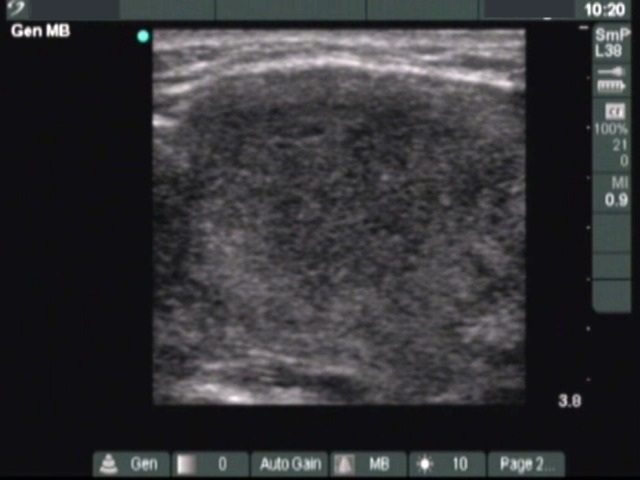

Subacute granulomatous de Quervain's thyroiditis - Case 2. (ultrasonographic picture 3)

Left lobe, longitudinal scan. Great part of the lobe is composed of a hypoechogenic lesion.